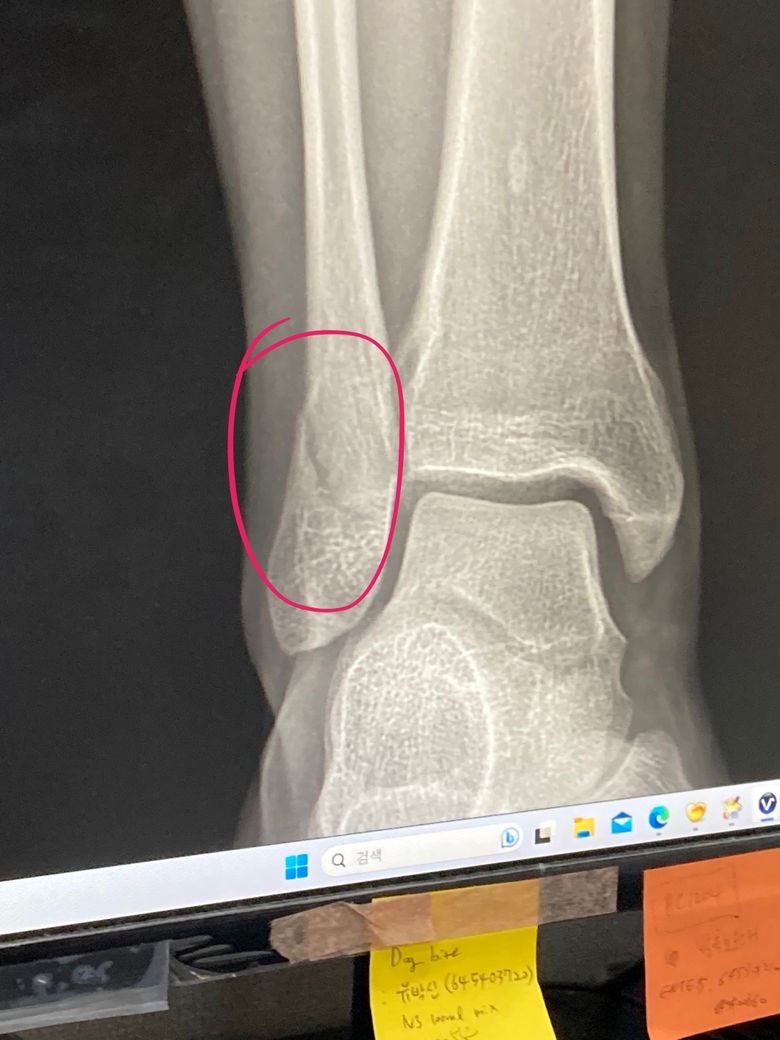

발목 골절 수술 해야하나요? 비골 골절 (x레이 첨부)

다친 직후 구급차 타고 간 병원에서 해당 엑스레이를 확인했고

입원 및 수술을 해야한다고 들었습니다만

전문가는 아니지만 x레이 상으로는 깔끔하게? 부러진 느낌이라

비수술적 치료로 갈라진 부분만 유합되면 괜찮을 것 같은데...

x레이상 비골이 제자리를 크게 벗어난거 같지 않은데

x레이 상 골절의 수술 or 비수술 치료에 대한 소견이 궁금합니다.

말씀하신대로 불유합이 매우 심해보이지는 않으나, 수술 여부는 x-ray 뿐만 아니라 인대, 힘줄 등의 손상 유무, 신체진찰, 개개인의 의학적 요소를 모두 고려하여 결정하기 때문에 되도록이면 진료본 주치의의 판단에 따르는 것이 좋습니다.

그럼에도 비수술적 치료를 원하신다면 다른 정형외과 방문하시어 상담 받아보시는 것을 권유 드립니다.